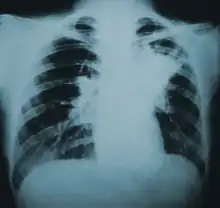

Lung infiltration in blastomycosis. | |

Blastomycosis manifests as a primary lung infection in about 79% of cases.[8] The onset is relatively slow and symptoms are suggestive of bacterial pneumonia, often leading to initial treatment with antibacterials. Because the symptoms are variable and nonspecific, blastomycosis is often not even considered in differential diagnosis until antibacterial treatment has failed, unless there are known risk factors or skin lesions.[8] The disease may be misdiagnosed as a carcinoma, leading in some cases to surgical removal of the affected tissue.[19] Upper lung lobes are involved somewhat more frequently than lower lobes.[20] If untreated, many cases progress over a period of months to years to become disseminated blastomycosis.

Blastomycosis in the lungs may present a variety of symptoms, or no symptoms at all.[8] If symptoms are present they may range from mild pneumonia resembling a pneumococcal infection to acute respiratory distress syndrome (ARDS).[8] Common symptoms include fever, chills, headache, coughing, difficulty breathing, chest pain, and malaise.[8] Without treatment, cases may progress to chronic pneumonia or ARDS.[8]